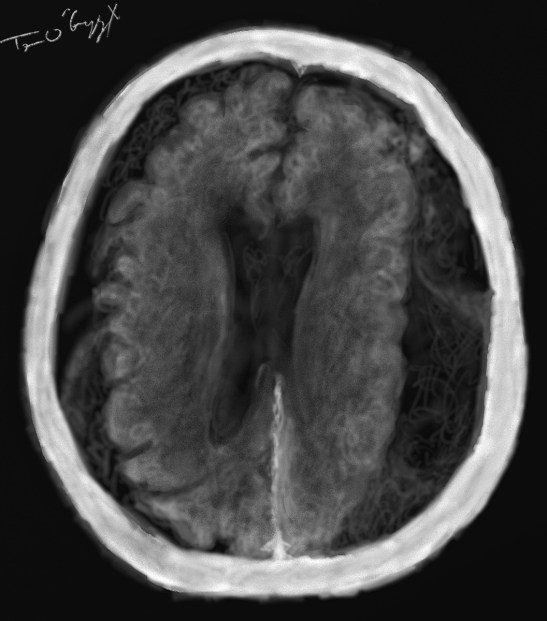

hématome sous dural bilatéral isodense, difficile à voir même après injectiond de produit de contraste

L’IRM peut bien évidemment visualiser des hématomes mais l’examen n’étant pas dans le bilan initial d’un traumatisme crânien ou d’un polytraumatisme, on observe peu ce genre de lésions sur cet examen. Néanmoins des IRM demandées dans des indications plus vasculaires et en neurovasculaire dans le bilan AVC avec possibilité de thrombolyse peuvent visualiser des hématomes sous duraux de petites tailles ainsi que d’autres lésions parenchymateuses associées. Elle peut aussi faire partie du bilan secondaire d’un HSD de petite taille surveillé cliniquement.